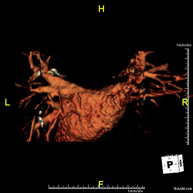

- Supra-aortic trunk MRI angiography

This non-invasive diagnostic procedure uses an electromagnetic field and radio waves (from a transmitter and receiver) to acquire high-definition anatomical images of the carotid and vertebral arteries in the neck. It is a radiation-free procedure. In most cases, paramagnetic contrast (gadolinium) is required. It enables non-invasive angiographic studies using a gadolinium injection, with subsequent 2D and 3D reconstruction using specialised workstations. Indicated for: cerebral circulatory problems, syncope.

- Angio-RM Troncos supraaórticos

Prueba diagnóstica no invasiva que consiste en la obtención de imágenes de alta definición anatómica de las arterias carótidas y vertebrales a nivel de cuello, mediante el empleo de un campo electromagnético y ondas de radio (con un emisor y un receptor). No utiliza radiación ionizante. En la mayoría de los casos es necesario el empleo de contraste paramagnético (Gadolinio). Permite un estudio angiográfico no invasivo gracias a la inyección de Gadolinio con posterior reconstrucción en 2D y 3D, gracias a estaciones de trabajo especializadas. Indicaciones: Problemas circulatorios cerebrales, síncope.